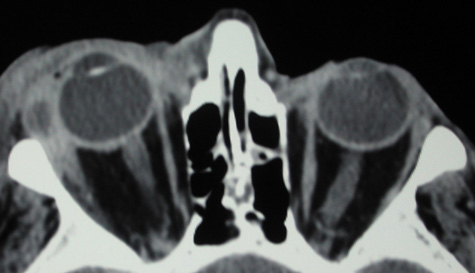

An extraconal or intraconal mass may be present in orbital cellulitis. Proptosis also may be visible. In particular, with intraconal involvement, proptosis is seen with obliteration of the normal soft tissue shadows. “Patchy enhancement” of the intraconal fat in orbital cellulitis has been described.59 The rectus muscles, particularly the medial rectus, and the optic nerve may be thickened.58

CT is particularly useful for imaging orbital and subperiosteal abscesses. Because the periorbit is not adherent to the orbital walls except at the suture lines, an abscess lifts the periorbit, creating a convexity in the orbital periosteum (Fig. 16). Usually subperiosteal abscess formation occurs adjacent to the involved sinus,25,64 but occasionally it occurs at a remote location such as the superolateral orbit.65 Gas may be found within a subperiosteal abscess or within the orbit, arising either from gas-forming bacilli or free communication with sinus air or from prior trauma (Fig. 17). 57,66 CT cannot accurately predict whether a subperiosteal mass represents exudate, inflammatory transudate, or hematoma.67,68

Fig. 16. Computed tomography showing subperiosteal abscess formation. Note elevation of orbital periosteum and convexity as pus elevates periorbit from the medial orbital wall.